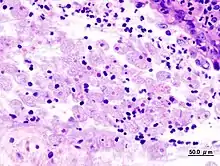

Quand les examens parasitologiques sont négatifs, le sérodiagnostic et la rectoscopie sont des examens d'appoints. Le sérodiagnostic est négatif dans les dysenteries aigües, mais il tend à devenir positif par la suite.

La rectoscopie montre une muqueuse inflammatoire et hémorragique avec des ulcérations « en coup d'ongle ». La biopsie colique peut montrer en phase aigüe les microabcès « en bouton de chemise », et en cas d'amœbome, un granulome inflammatoire.

Les examens radiologiques du colon sont non spécifiques. Ils peuvent montrer des zones ulcérées (amœbiose aigüe), spasmées en « piles d'assiettes » (colopathie post-amibienne), ou un aspect pseudo-tumoral (amœbome).

Dans les formes extracoliques, l'échographie ou le scanner montrent les abcès du foie ou d'autres organes. En règle générale, dans ces formes évoluées, la recherche d'amibe est alors négative, mais la sérologie plus souvent positive[11],[26].